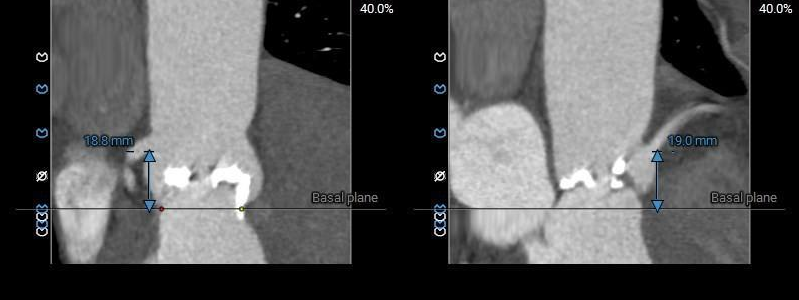

术前CT评估

Type0型二叶式主动脉瓣,LVOT偏敞口型,非横位心。

重度钙化,HU 850积分1711mm3。

左冠18.8,右冠19,综合分析冠脉阻挡风险适中。

瓣上多平面分析。